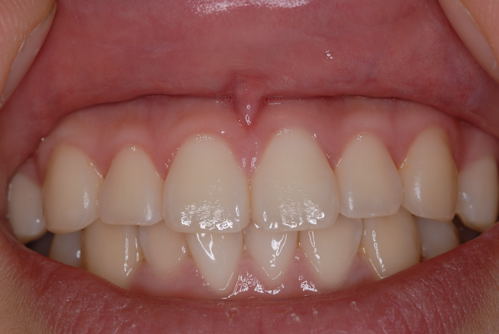

| 健康な歯肉です。色が全然違いますね。健康な歯肉は薄いピンク色なのです。 | ![]() |